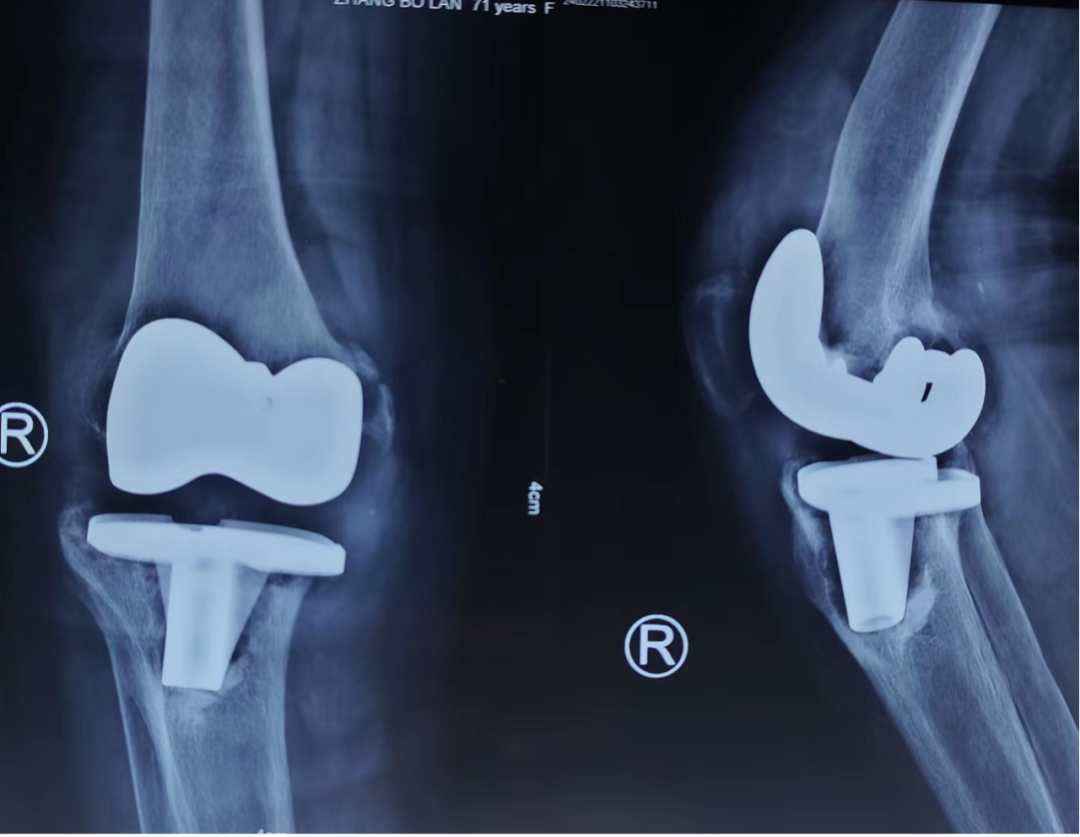

患者张某,女,71岁,因“右膝关节反复肿胀疼痛伴活动受限半年余”来我院,询问病史得知于2012年行右膝关节置换手术,复查膝关节DR片提示:右侧膝关节置换术后假体松动,半年来右膝关节病情已严重影响日常生活,患者及家属手术意愿强烈。入住后朱雄主任医师高度重视,经认真研究讨论病情,最终决定为患者行右膝LCCK翻修手术,手术难点在于重建胫骨骨缺损、纠正软组织失衡,以最小限制性达到最大关节稳定性,同时还要控制翻修手术的高感染率难题。